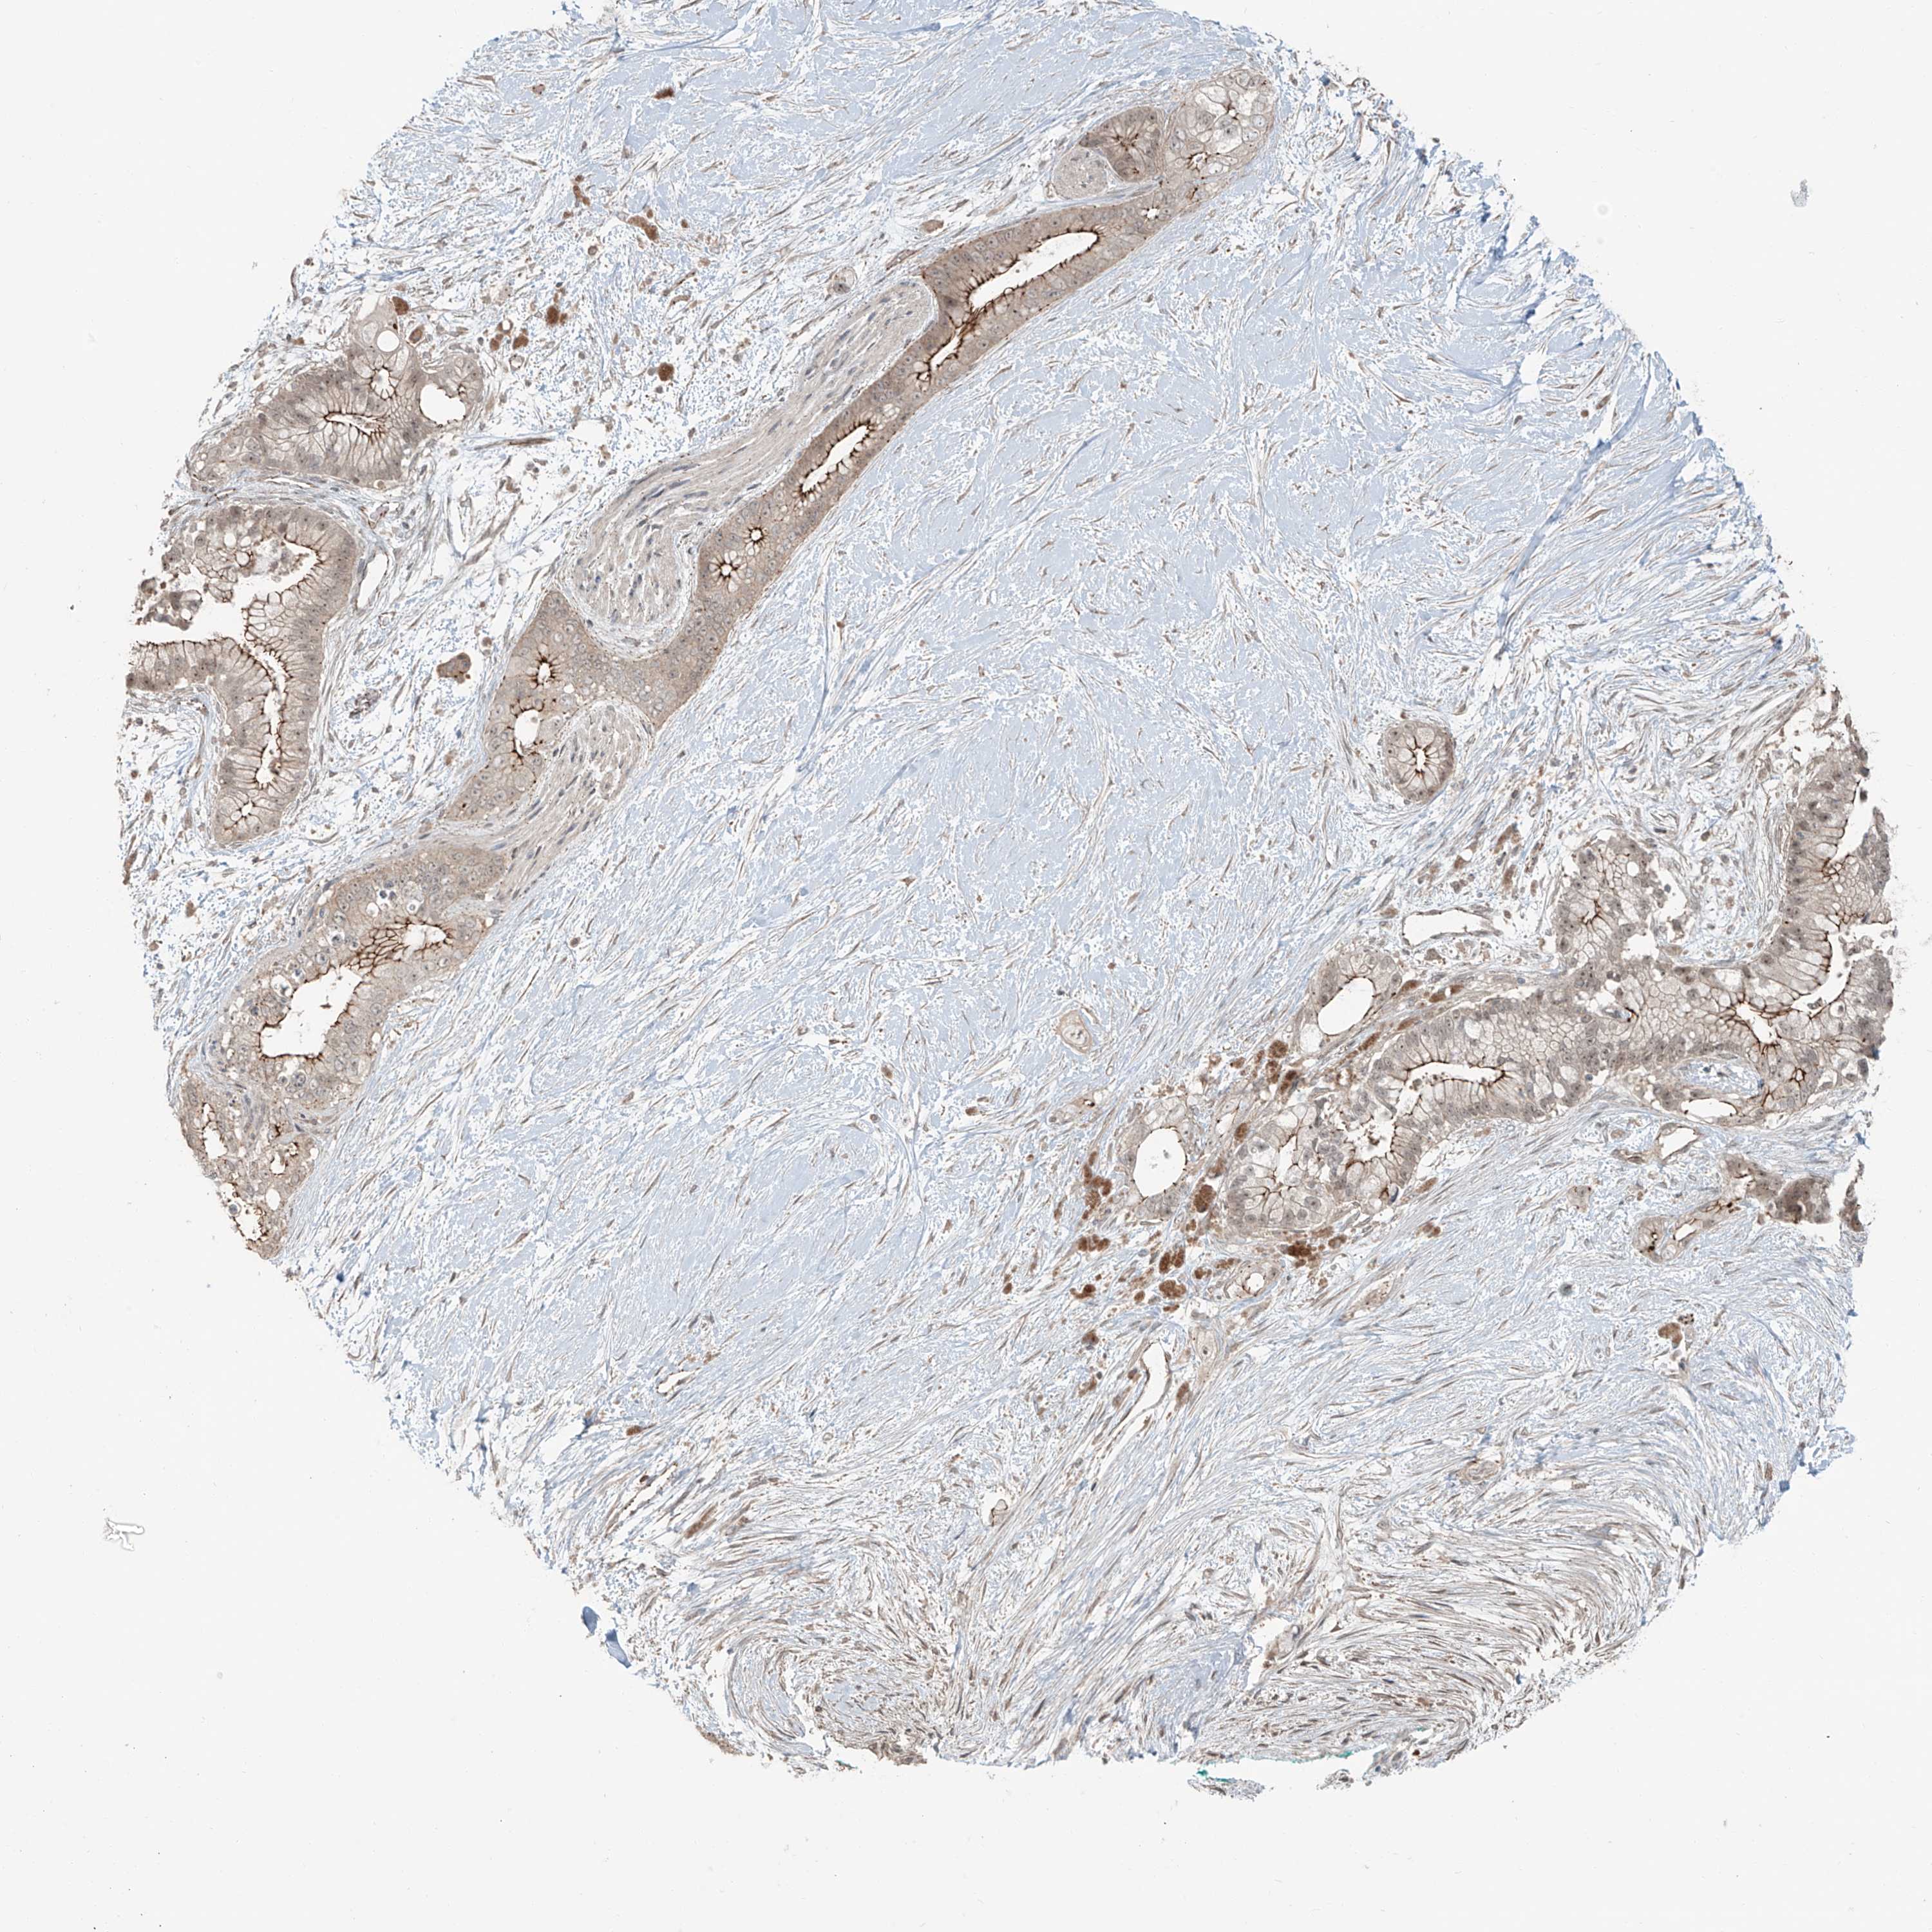

PANCREATIC CANCER - Protein expressioni

A mouse-over function shows sample information and annotation data. Click on an image to view it in a full screen mode. Samples can be filtered based on level of antibody staining by selecting one or several of the following categories: high, medium, low and not detected. The assay and annotation is described here.

Note that samples used for immunohistochemistry by the Human Protein Atlas do not correspond to samples in the TCGA dataset.

Antibody stainingi

Antibody staining in the annotated cell types in the current human tissue is reported as not detected, low, medium, or high, based on conventional immunohistochemistry profiling in selected tissues. This score is based on the combination of the staining intensity and fraction of stained cells.

Each image is clickable and will lead to virtual microscopy that enables deeper exploration of all samples and also displays staining intensity scores, fraction scores and subcellular localization as well as patient and tissue information for each sample.

Antibody HPA035782

Staining

High

Medium

Low

Not detected

Intensity

Strong

Moderate

Weak

Negative

Quantity

>75%

75%-25%

<25%

None

Location

Nuclear

Cytoplasmic/membranous

Cytoplasmic/membranous,nuclear

Adenocarcinoma, NOS